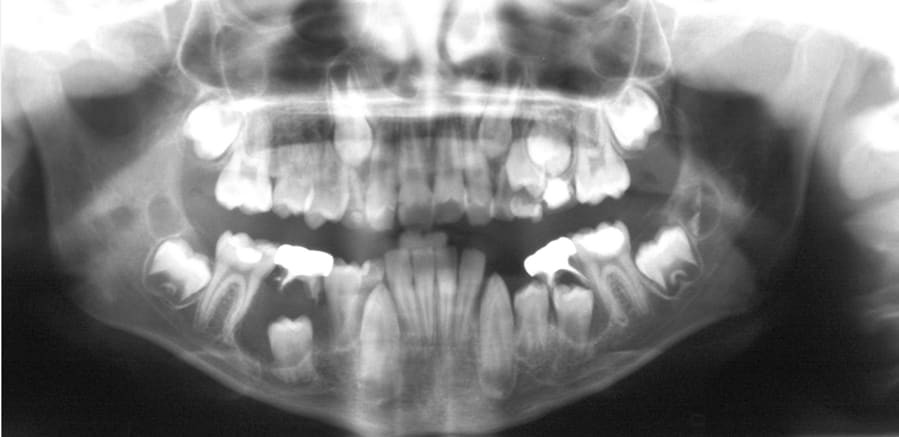

Dentigerous cyst, causes and treatment

Dentigerous cysts are the second most common type of odontogenic cyst, which is a fluid-filled sac that develops in the jaw bone and soft tissue. They form over the top of an unerupted tooth, or partially erupted tooth, usually one of your molars or canines. While dentigerous cysts are benign, they can lead to complications, such as infection, if left untreated.

How is it diagnosed?

Small dentigerous cysts often go unnoticed until you have a dental X-ray. If your dentist notices an unusual spot on your dental X-ray, they may use a CT scan or MRI scan to make sure it’s not another type of cyst, such as a periapical cyst or an aneurysmal bone cyst.